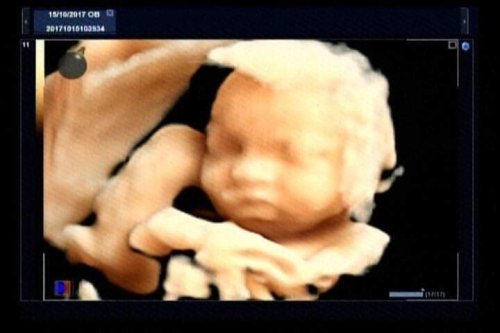

Khi mang thai, siêu âm cho nhiều giá trị chẩn đoán và giúp phát hiện những bất thường trong quá trình mang thai. Thông thường trong mỗi lần mang thai, tối thiểu sản phụ cần siêu âm 3 lần vào các mốc sau: 11-14 tuần, 18-22 tuần và 30 - 32 tuần.

- Siêu âm thai định kỳ là việc làm rất cần thiết để theo dõi quá trình mang thai và kịp thời phát hiện được các bệnh tiềm ẩn của thai nhi cũng như thai phụ. Siêu âm là phương tiện chuẩn đoán hình ảnh giúp đánh giá sức khỏe của phụ nữ mang thai. Đây cũng là một kỹ thuật an toàn, chính xác và đơn giản.

Tại Phòng khám đa khoa Cao đẳng Y tế Thanh Hoá quy tụđội ngũ y, bác sĩ giàu kinh nghiệm, trình độ chuyên môn cao. Cùng sự hỗ trợđắc lực của hệ thống trang thiết bị y tế hiện đại, đặc biệt là hệ thống máy siêu âm Accuvic A30 và máy siêu âm Volusun P8 sẽ giúp tầm soát dị tật thai nhi một cách hiệu quả nhất như: tim bẩm sinh, hội chứng DOWN...Ngoài ra phòng khám còn triển khai làm các xét nghiệm như: NIPT, DOUBLE test, TRIPLE test, tiểu đường.....